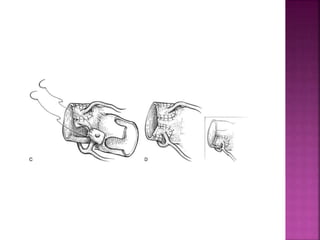

 Persistence of sub Aortic conus and

absorption of sub pulmonary conus

 Failure of the Truncus Arteriosus to septate

normally

 Persistence ofsub Aortic conus and absorption of sub pulmonary conus  Failure of the Truncus Arteriosus to septate normally